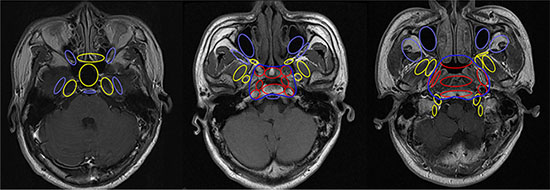

Clinical target volume (CTV) was delineated individually based on GTV, patterns of loco-regional extension and biological characteristics of NPC. The CTV for GTVnx included CTV1 for high risk regions and CTV2 for low risk regions of microscopic infiltration. CTV1 was defined as GTVnx plus a 5–10 mm margin, including the entire nasopharyngeal mucosa and structures within the pharyngobasilar fascia. For CTV2, firstly, bilateral anatomic sites at high risk, including parapharyngeal space, posterior part of nasal cavity, pterygoid process, prevertebral muscle, clivus, petrous apex, foramen lacerum and basis of sphenoid bone, were included in each patient (Figure 2). Then, downstream anatomic sites adjacent to involved sites along routes of tumor infiltration were prophylactically irradiated (Figure 3). Finally, the margin of both CTVs could be reduced to 2–3 mm at the sites of brain stem, spinal cord and temporal lobes and margins could be limited to exclude bone or air spaces not at risk of subclinical disease.

Figure 2: Relationship between the CTV2 and risk of tumor extension. Anatomic sites shown in red are at high risk of tumor invasion; yellow, medium risk; and light blue, low risk. The dark blue line represents the smallest CTV2 area for primary tumor.